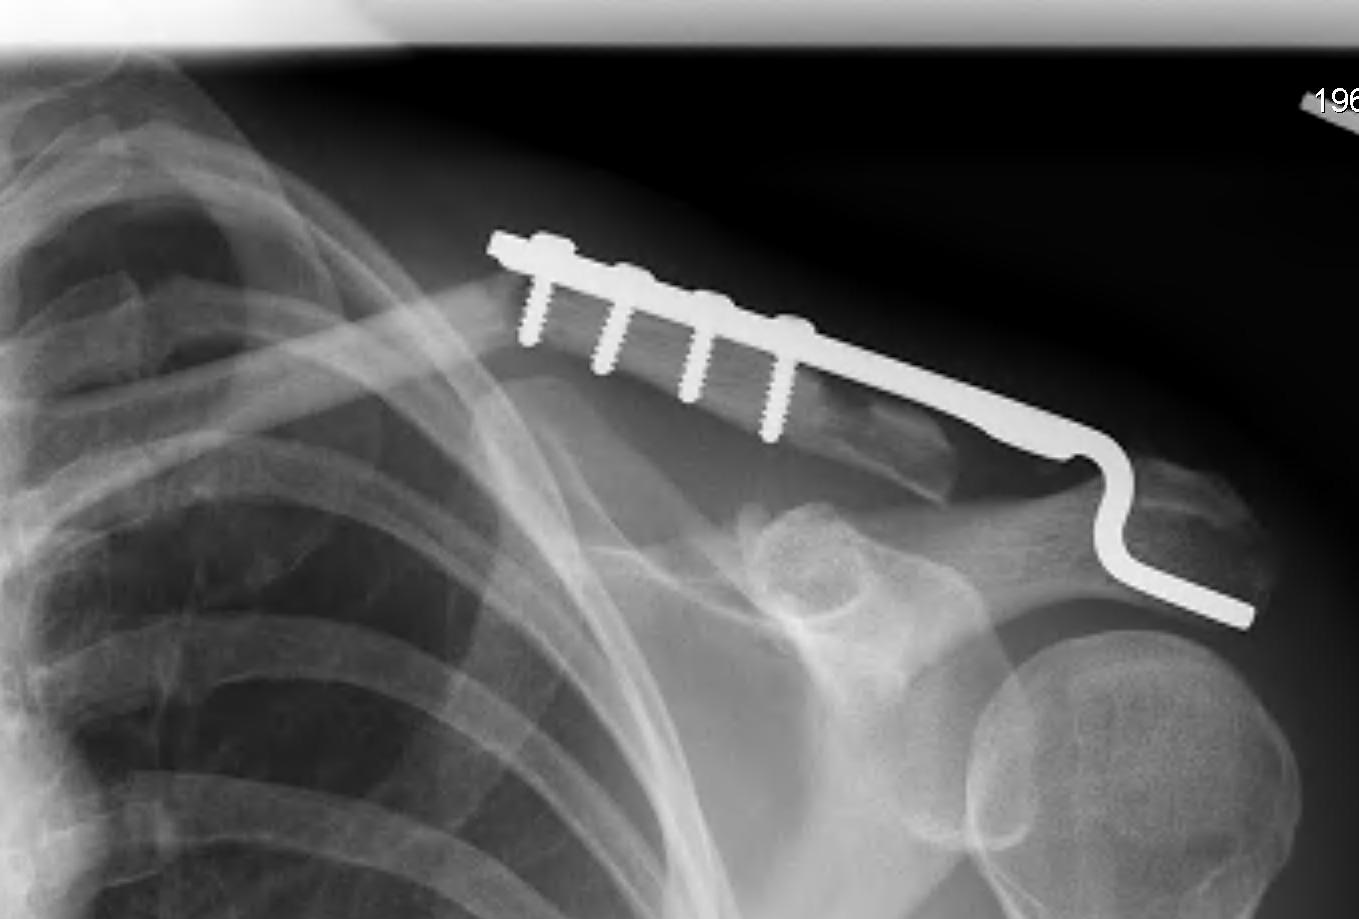

Hook plate

Technique

Reduction of ACJ

- hook under posterior acromion

- allows CC ligaments to heal

- need to remove plate at 4 - 6 months

Risks

Subacromial erosion - may be reduced by increasing the angle on the hook

Hook plate cut out through acromion - need to remove hook plate at 6 - 8 weeks

Clavicle fracture at end of plate

Hemmann et al Arch Orthop Trauma Surg 2021

- 99 patients with acute ACJ dislocation treated with hook plate

- average loss of reduction of 4 mm after hook plate removal

- nearly all good to excellent outcome

- 68% full ROM post operatively